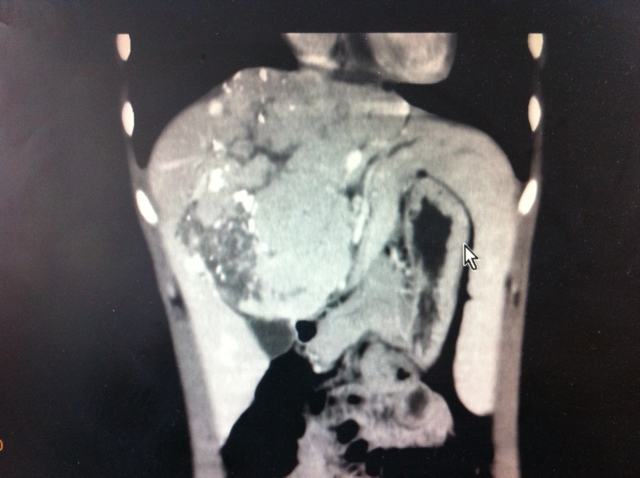

我院CT检查显示:肝中叶巨大肿块,大小约11*12cm,严重包裹或压迫肝脏血流的流入道和流出道。左、右肝动脉和左、右门静脉为肝脏的4支主要供血血管,左、中、右肝静脉为3支流出血管。而小雨的肝脏肿块包裹了左肝动脉、左门静脉、左肝静脉和中肝静脉,同时严重压迫右肝静脉、右肝动脉、右门静脉(图1)。

“可以说,这如同横架在小雨肝脏所有重要血管上的定时炸弹,很可能在不久的将来夺走其年轻的生命,手术切除好比拆除炸弹,”小雨的主管医师罗宏武教授在分析病情时说道。但面对小雨母亲几近哀求的目光,考虑到小雨年仅19岁,罗教授毅然决定实施手术。